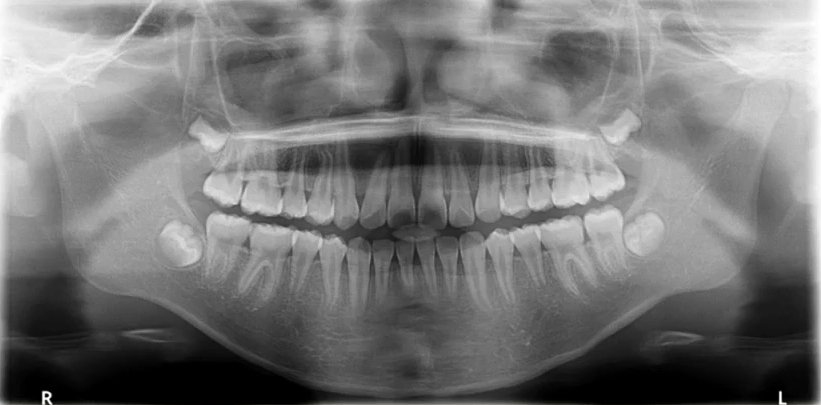

一、理想曲断影像

中线左右对称,牙齿排列呈微笑弧形,片子左右两边相对对称,能清晰显示颞下颌关节、上下牙列的牙根,图像的对比度和分辨率较好。

1. 先整体后局部,有顺序不遗漏

因为曲面断层片反映的是上下颌牙齿、上颌窦、关节,在一张片子中所展示的解剖结构较多。比如刚才的片子,最容易诊断的是右下6远中邻面深龋合并根尖周炎,左下有埋伏的多生智齿,右侧是垂直智齿。

注意不要遗漏,比如片子中显示上颌两个3是缺失的,是先天性缺失还是做过手术?有可能会漏掉一些临床信息。

2. 推荐象限顺序

1(右上)→2(左上)→3(左下)→4(右下)

3. 推荐检查部位顺序

牙→骨→上颌窦→关节

比如患者右侧髁突的前斜面发生了硬骨改变。

4. 左右对称比较

左、右下5根方有低密度影,一般认为是颏孔位置,左右对称进行观察可以排除一些疾患。